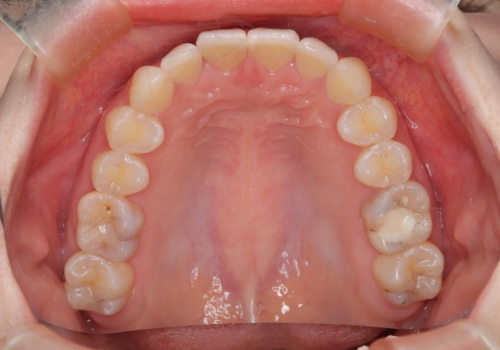

前歯のガタつきを治したい 翼状捻転マウスピース矯正

- 上顎前歯の突出、がたつき(翼状捻転)を主訴に来院されました。当院では総合歯科医療が可能であるため、矯正前処置として虫歯治療・歯周治療、親知らず抜歯を施行しました。その後、非抜歯かつ口元が出ないようなマウスピース治療を行いました。仕事柄、1日の装着時間が短くなってしまう時期もありましたが、患者様と相談しながら問題なく終了しています。